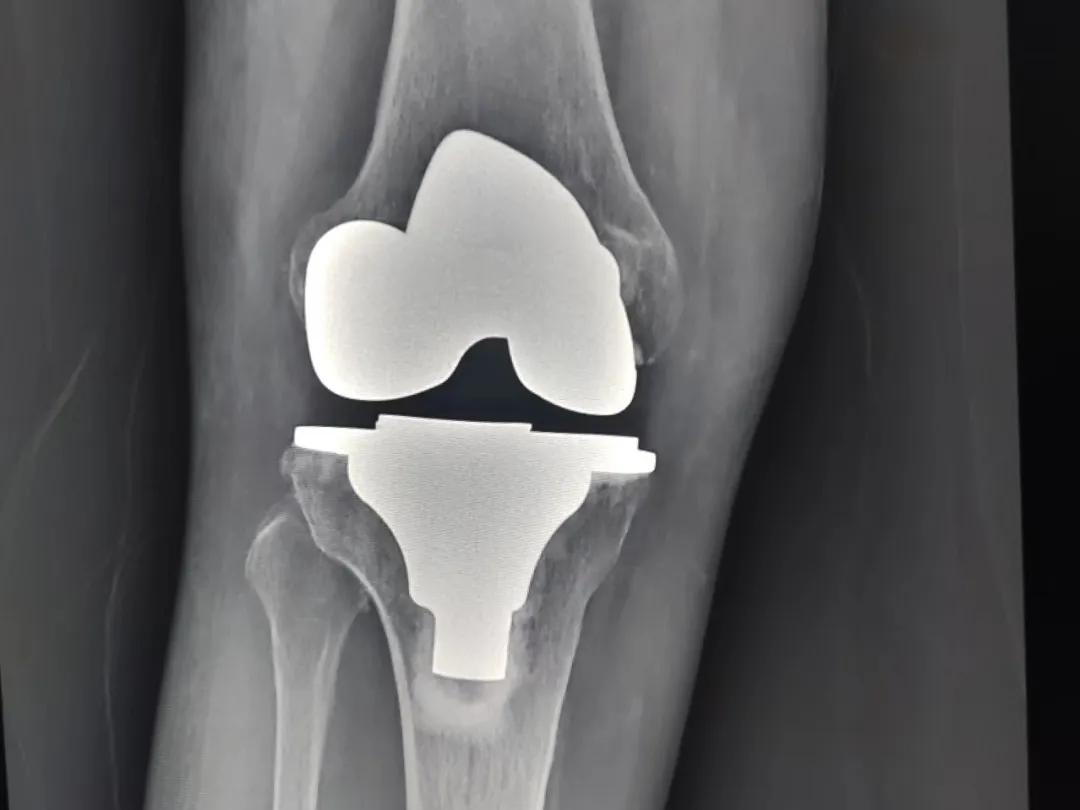

得了骨关节炎,什么时候该考虑膝关节置换?很多朋友都被这个问题难住🤔 其实核心判断标准很明确👇 ✅ 非手术治疗彻底“失灵”:吃药、打针、理疗、针灸都试了个遍,疼痛还是没缓解,甚至越来越重,连走路、上下楼都费劲,已经严重影响日常生活,那别硬扛了,该考虑手术了💪 ✅ 关节结构“破相”严重:拍X光片能看到关节间隙明显变窄,甚至消失,骨质磨损严重,还长了大量骨刺,这说明关节软骨已经磨得差不多了,保守治疗已经回天乏术。 ✅ 已经拧成“歪腿”:出现明显的膝内翻(O型腿)或者膝外翻(X型腿),走路都晃悠,关节稳定性越来越差,这种畸形靠保守矫正是纠正不了的,得通过置换手术重新理清楚力线。 ✅ 活动范围“锁死”:膝盖弯不下去也伸不直,穿袜子、系鞋带都成了难事,连坐椅子站起来都费劲,生活质量大打折扣。 就像江门那位68岁的钟阿姨,被骨关节炎折磨了20多年,最后痛到寸步难行,双腿都变成O型了,做完膝关节置换术后第二天就能下地走,疼痛感直接消失✨ 不过也要提醒大家,膝关节置换不是想做就能做,得先让医生评估你的身体状况,有没有感染、严重内科疾病这些禁忌症。如果真的符合手术指征,别因为害怕手术就一直忍,现在的关节置换技术已经很成熟了,很多人做完都能重新回到正常生活~ 觉得有用就转给身边被膝痛困扰的朋友吧!健康知识 膝关节置换